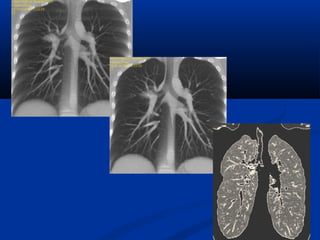

Xaùc ñònh vò tríxöông söôøn treân CT

NOÄI SOI AÛOPHEÁ QUAÛN